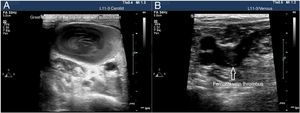

The tracheal ultrasound has proven to be non-inferior to capnography to rule out esophageal intubation.17 For this purpose, it is necessary to use a linear or convex transducer and acquire the cross-sectional view from the anterior region of the neck, in the mid-line above the sternal notch. In this plane, the trachea looks like a hyperechogenic inverted U-shaped line generated by the mucosa-air interface and a posterior comet-tail artifact (Fig. 1A). The correct intubation of the trachea does not cause any changes in the image described since no new interface between the patient’s airway and the OTT is generated (both contain air). Also, because the OTT is located behind the artifact generated by the trachea (which would limit its visualization). On the echocardiography, the accidental intubation of the esophagus generates a new interface between the esophageal mucosa and the air inside the OTT giving rise to a second comet-tail artifact that originates at the deepest level of the trachea and is lateral to it (Fig. 1B). The main advantage of this type of study is that ventilation does not need to be started to detect the incorrect position of the OTT, thus avoiding the possibility of aspiration of gastric content; its limitations are the impossibility to see the OTT directly from inside the airway and the patient’s possible anatomical alterations.

Utility of the tracheal and pleural ultrasound for OTI verification purposes. A) Tracheal ultrasound image showing the trachea with its posterior acoustic shadow surrounded by the thyroid. B) Tracheal ultrasound image with the transducer displaced towards the neck left region. The arrow points at the esophagous. C) Pleural ultrasound image with normal airing pattern indicative that the lung is insuflated. D) Pleural ultrasound image with bar code sign indicative that the lung is not insuflated. Possible contralateral selective intubation.

Pleural ultrasonography provides direct anatomical information on the expansion of the lungs and entry of air into the lungs.18 It can replace auscultation and chest x-rays as the method to rule out accidental selective bronchial intubation (ASBI). For this purpose, it is required to use a linear or convex probe to examine, at least, the upper and lower points of the BLUE protocol in both hemithoraces.19 In these planes, on the 2D ultrasound, the pleura appears as a horizontal hyperechogenic line with movement generated by the slide of the parietal pleural surface over the visceral pleura with respiratory movements called lung sliding or lung displacement sign.20 On M-mode it can also be registered statically by cutting the pleural line producing an image called seashore sign. The presence of both signs in each hemithorax is indicative of bipulmonary insufflation (Fig. 1C). The consequence of ASBI is the lack of airing of the contralateral lung that can be found by the absence of lung sliding and a typical «bar code» pattern or stratosphere sign on M-mode (Fig. 1D). The transformation of a unilateral bar code pattern into a normal lung sliding pattern associated with the partial removal of the OTT is indicative that the initial position of the tube corresponds to an ASBI of contralateral lung (Fig. 7). The main advantages of this kind of examination are the possibility of showing the airing of the lung without having to use the stethoscope and its immediacy compared to the chest x-ray. The main limitation is the existence of differential diagnoses of the stratosphere sign (lack of ventilation, pneumothorax, tumors, etc.).